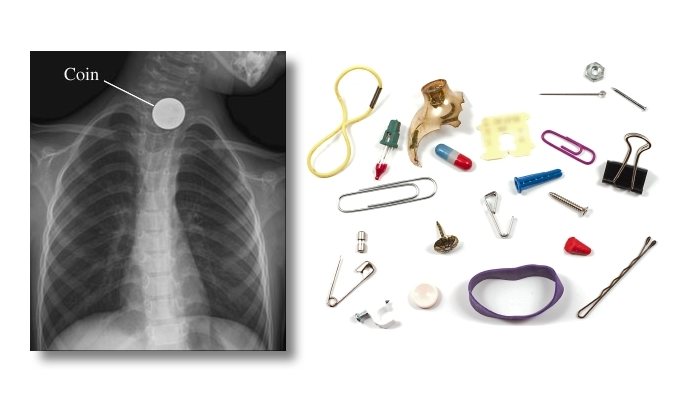

قد يكون ما تعانى منه سببه وجود جسم غريب عالق فى حلقك كعظمة سمك مثلا ، و هذه الحالة تعد من الحالات الطارئة التى ننصحك فيها بشدة بالمتابعة الطبية الفورية